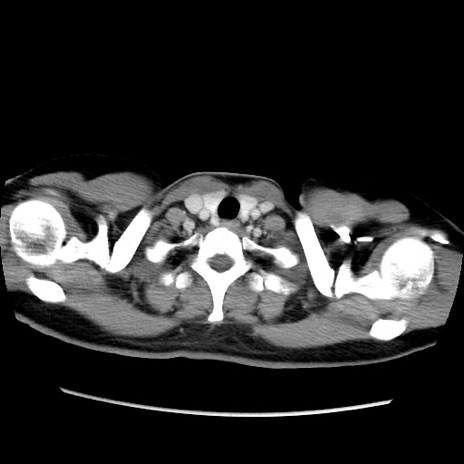

MRI(4日後)

【症例】40歳代女性

【主訴】上下腹部痛

【現病歴】2日目から下腹部痛あり。夜間は痛みで眠れなかった。昨日より上腹部痛と下痢が出現。臥位で痛みは軽快したため、休んでいた。本日になって臥位でも立位でも痛みが強くなってきたため救急要請。

【既往歴】子宮内膜症

【身体所見】部:平坦・軟、左上下腹部に圧痛あり、反跳痛あり。

【データ】WBC 21800、CRP 26.78